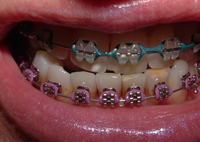

• Khí cụ cố định thường bao gồm các mắc cài, dây cung và khâu được gắn chặt lên răng lúc bắt đầu điều trị và chỉ được tháo ra khi hoàn tất điều trị, bệnh nhân không cần phải thao tác gì cả.

• Các mắc cài nếu bằng kim loại thì sẽ có màu kém thẩm mỹ nhưng hiện nay đã có một số loại mắc cài thẩm mỹ làm bằng mắc cài sứ, composite, hoặc đá, có màu như men răng nên khi mang sẽ đẹp hơn. Các loại thun đàn hồi có nhiều màu sắc được gắn vào mắc cài để giữ dây cung vào các mắc cài và khâu, đồng thời tạo lực trên dây cung và răng.